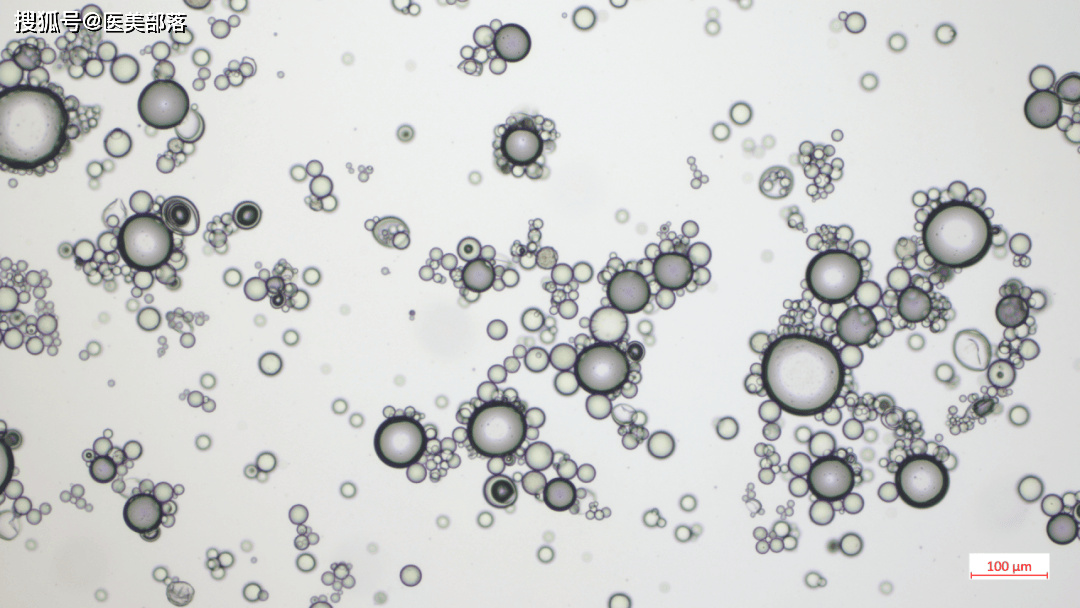

抛光微球冻干粉:工艺革新,微球形态优化为圆形,改善微球分布均匀性,实现胶原类型有序转化将III型胶原升级至 Ⅰ 型胶原。

图|某CaHa微球在电镜和显微镜下的展示